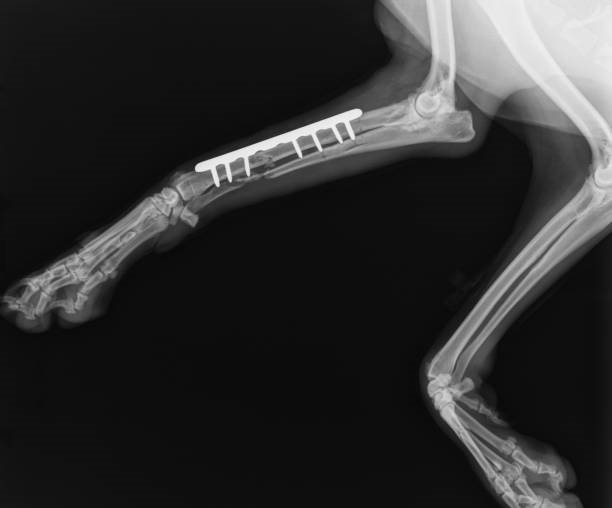

Os exames de raio x em cachorro em curitiba são fundamentais para a saúde, pois possibilitam aos veterinários diagnosticar diversas condições de saúde que não são visíveis a olho nu.

Seja para investigar uma possível lesão, identificar a presença de corpos estranhos ou acompanhar o desenvolvimento de uma doença, o raio x é uma ferramenta indispensável para o diagnóstico veterinário.